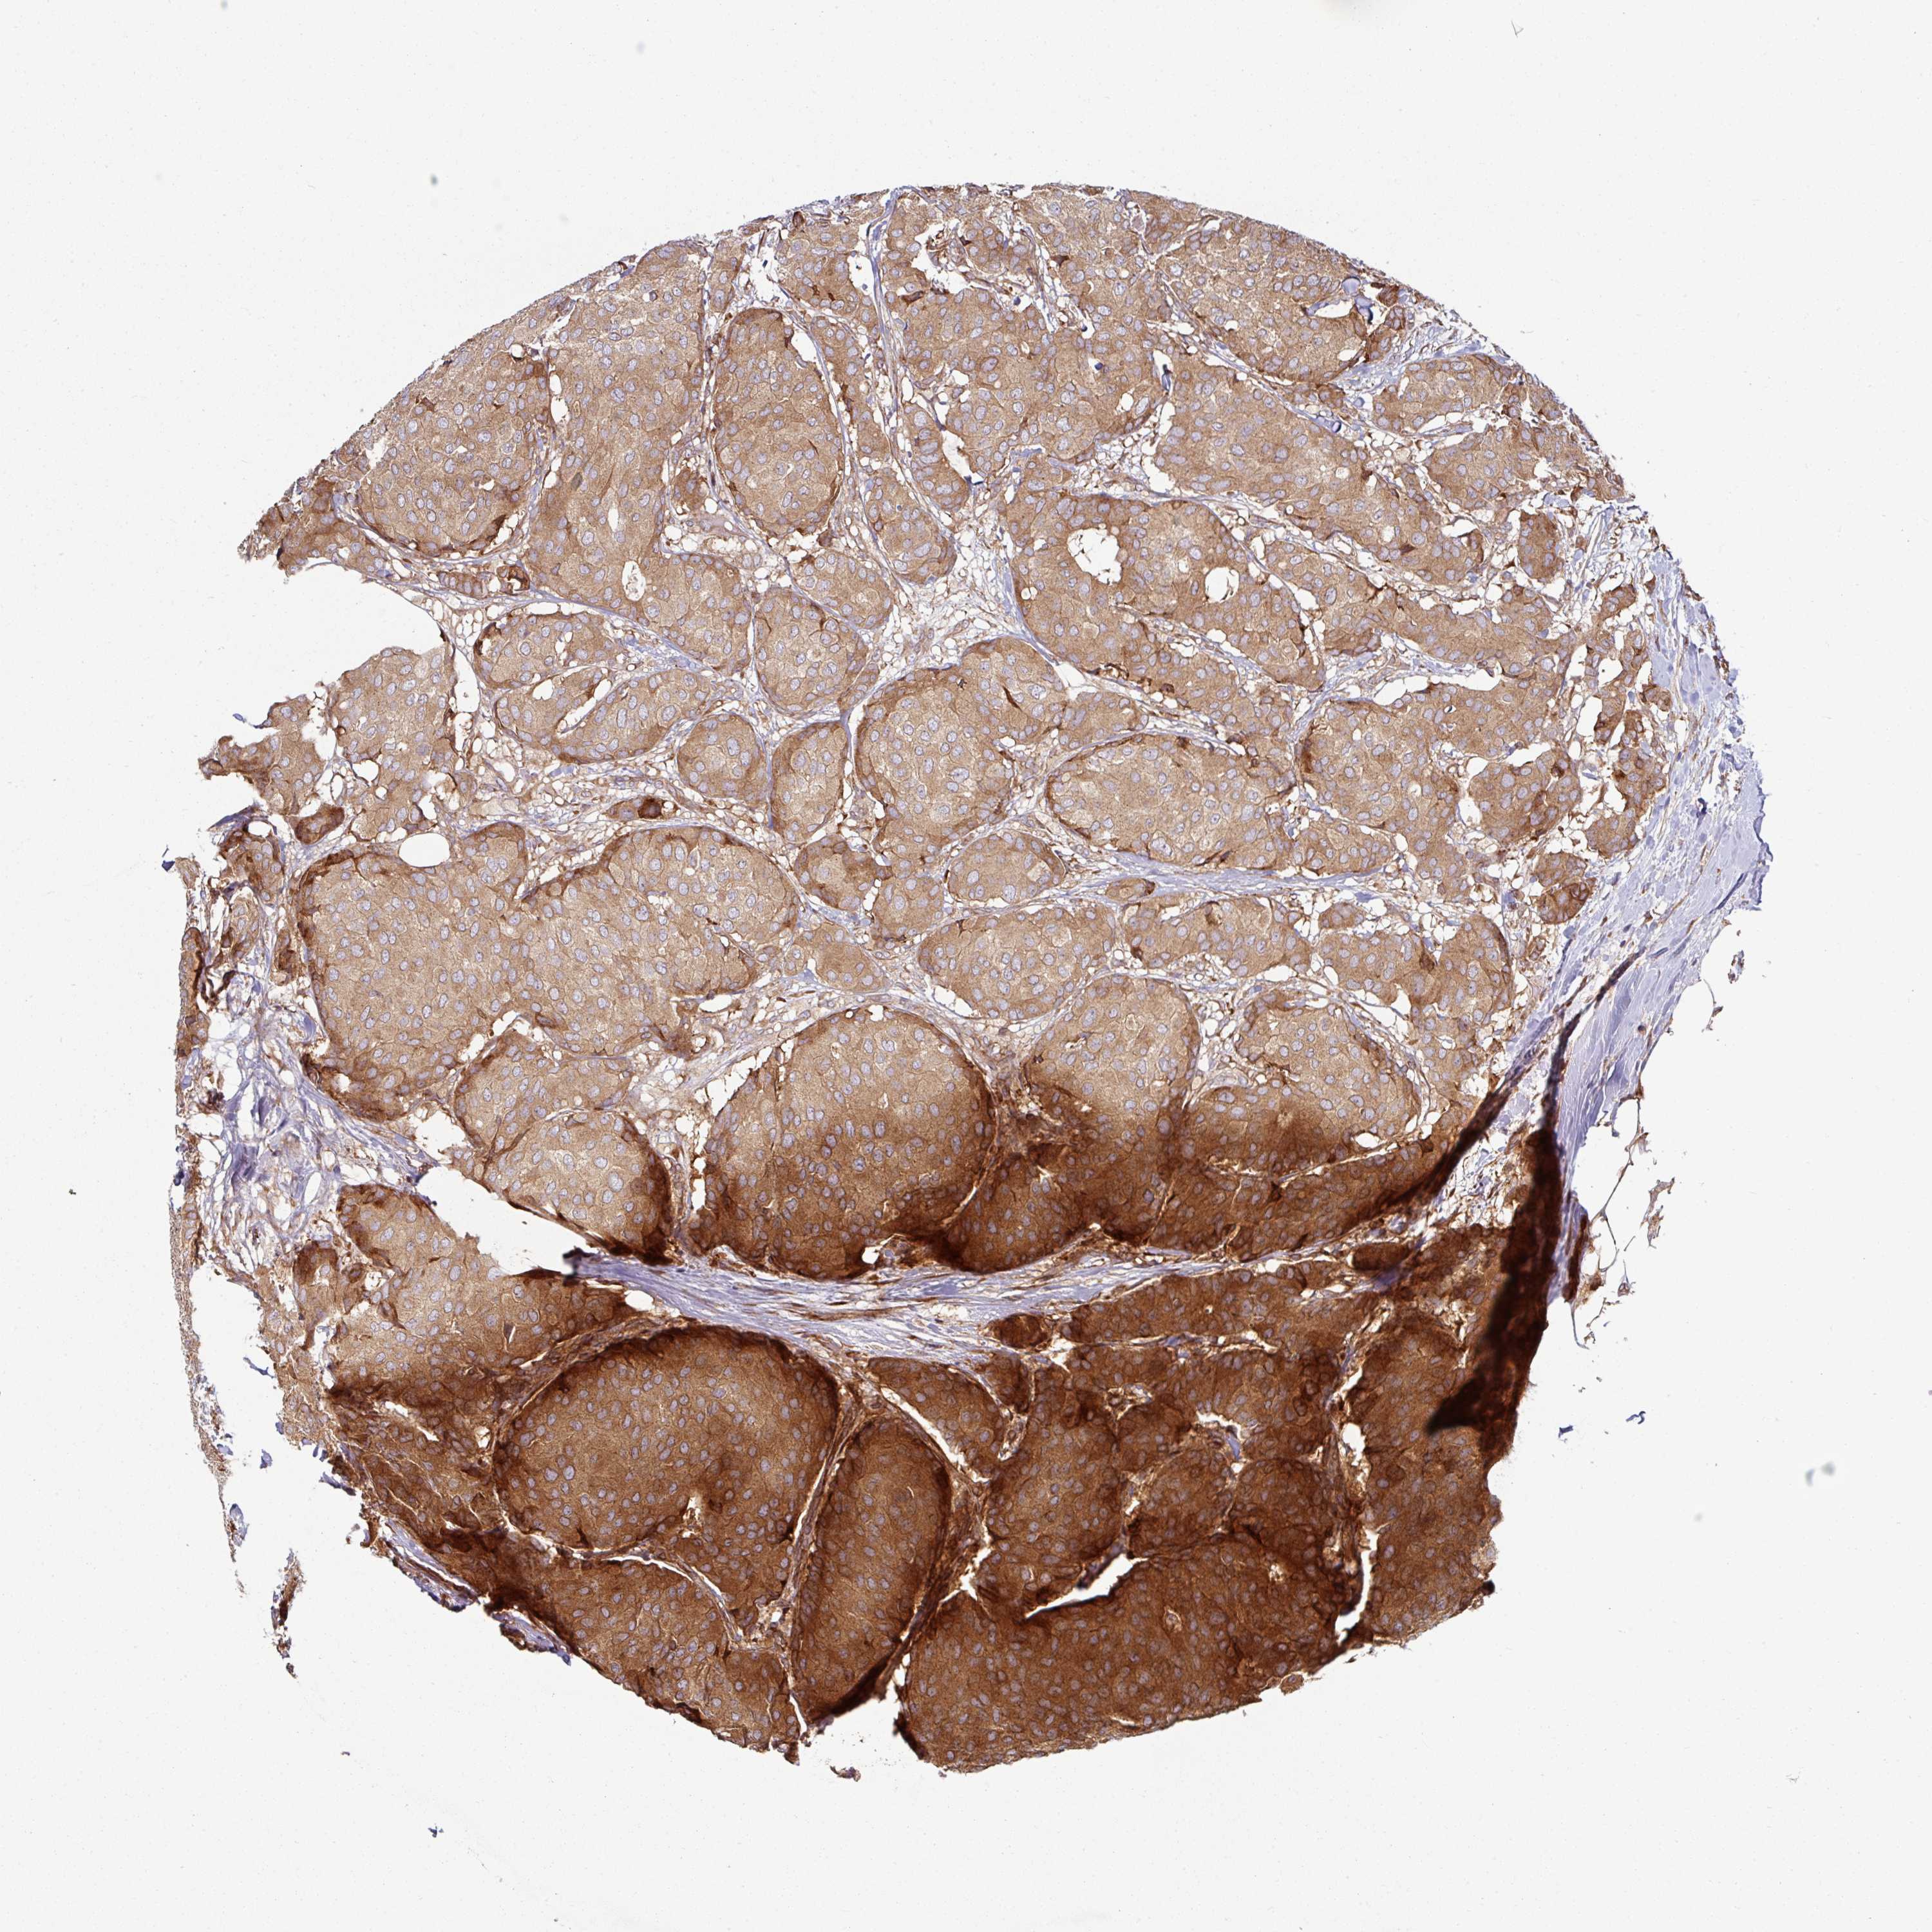

CANCER BREAST CANCER Show tissue menu

BRCA TCGA BRCA VALIDATION PROTEIN EXPRESSION